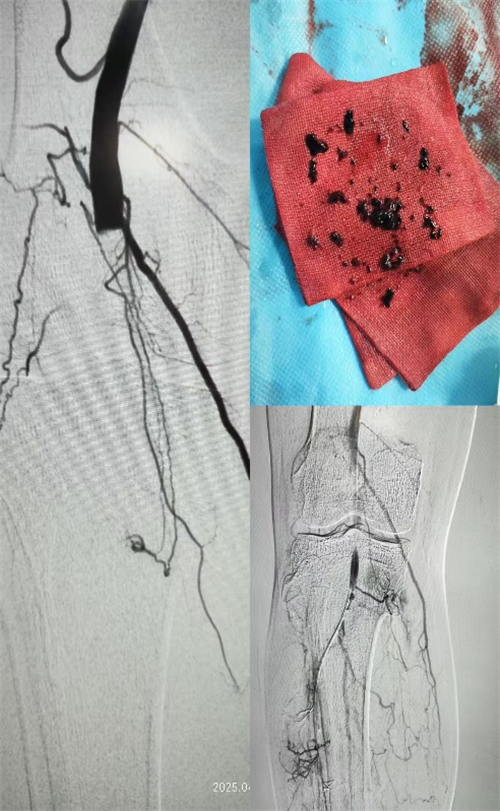

37小时后,医护团队再次出击,在局麻DSA下为患者进行双下肢动脉造影+导管内吸栓+下肢动脉导管溶栓术,又抽出约25克陈旧性血栓。术后,护理团队迅速进入“精细化”模式,用压迫器为患者加压止血,每30分钟就仔细巡视检查穿刺点,确保没有渗血、血肿;每小时触摸足背动脉搏动,监测皮肤温度与颜色变化,不放过任何一个细微异常。

第二期手术